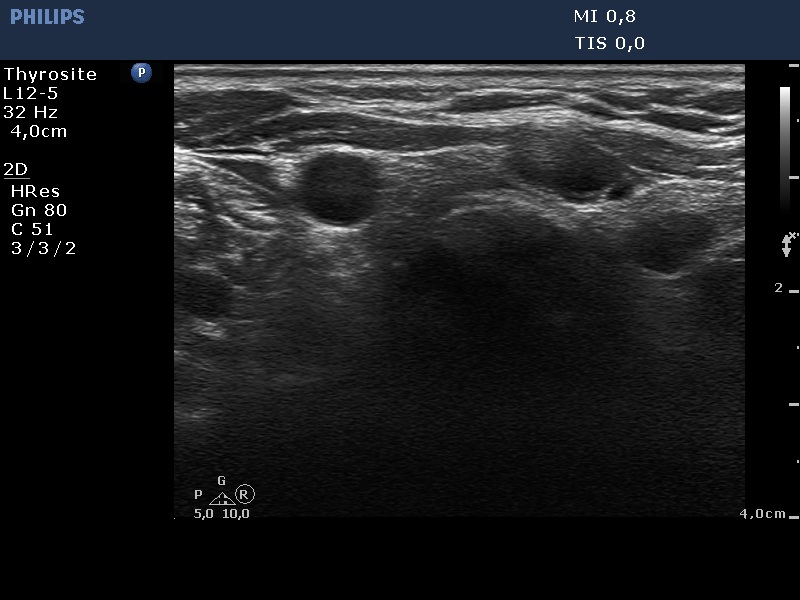

Ultrasound. Connective tissue replaced the thyroid parenchyma in both thyroid beds. There were tiny hypoechoic areas in the right thyroid bed. Two larger hypoechoic lesions were found, one in the isthmus and the other in the left thyroid bed. The latter presented vascularity.

Comment. The presentations of the hypoechoic lesion in all three sites were the same, they differed only in their size. Naturally, the two larger in the isthmus and in the left thyroid bed could cause and did cause concern. Especially that in the left lobe due to its intralesional vascularity. The larger lesions can correspond to small muscle fibers, remnant of the regenerative provess after the surgery but even damaged, non-viable thyroid tissue. Taking the thyroglobulin level into account, the risk of thyroid cancer is minimal but not zero.